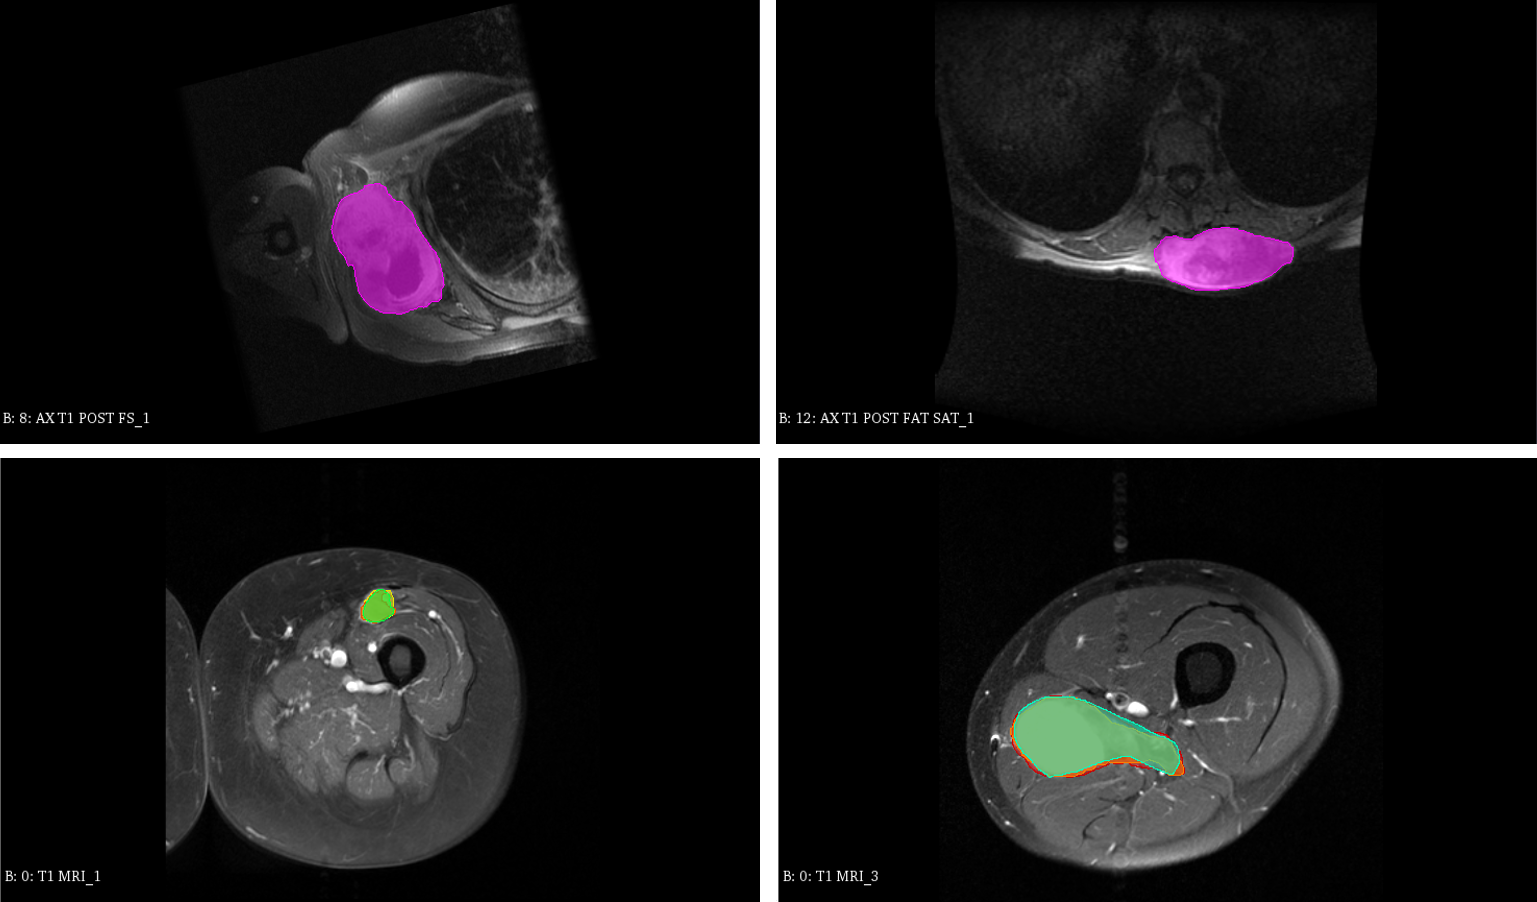

3D MRI Scan of Sarcoma Tumors (?) are sets of magnetic resonance imaging (MRI) scans of patients with sarcoma soft-tissue cancer. Clinical outcome were recorded including time-to-death censored from the day of scan acquisition and diagnosis. The goal is to classify whether the patients would survive longer than 1096 days ( 3 years) after diagnosis. In this study, censored patients due to loss of followup are considered that they survived longer than 1096 days. Pre-treatment contrast-enhanced T1-weighted 3D MRI scans are acquired from two independent cohorts of patients diagnosed with biopsy-proven soft tissue Sarcoma (STS) from two different institutes of censored institute1 (cohort1) and censored institute2 (cohort2). The acquisition is done with institutional picture archiving and communication system (PACS) standard with similar image matrix and resolutions. All patients that were less than 18 years old or were diagnosed with Kaposi or primary bone sarcomas were excluded. Included patients had sarcomas of various histologies of the extremity, trunk, or retroperitoneum. This study focused on American Joint Committee on Cancer (AJCC) version 7 stage II-III patients only, which encompasses non-metastatic patients with large (i.e. cm) and/or higher grade (i.e. ) tumors. Patients with image artifacts due to multiple MRI acquisitions within the tumor area were also excluded. The total number of patients in two cohorts were 200 and 72 patients, respectively. First 200 patients from cohort 1 were randomly separated into a training set of 180 images validation set of 20 images. Patients in cohort 2 were used for testing set. In all datasets, expert radiation oncologista evaluated each image for quality and manually segmented the gross tumor as ROI. Figure 3 visualize some sample in our datasets. Each scan’s ROI is resampled to have fixed resolution of 1 . All image ROIs are then resampled again into voxels.